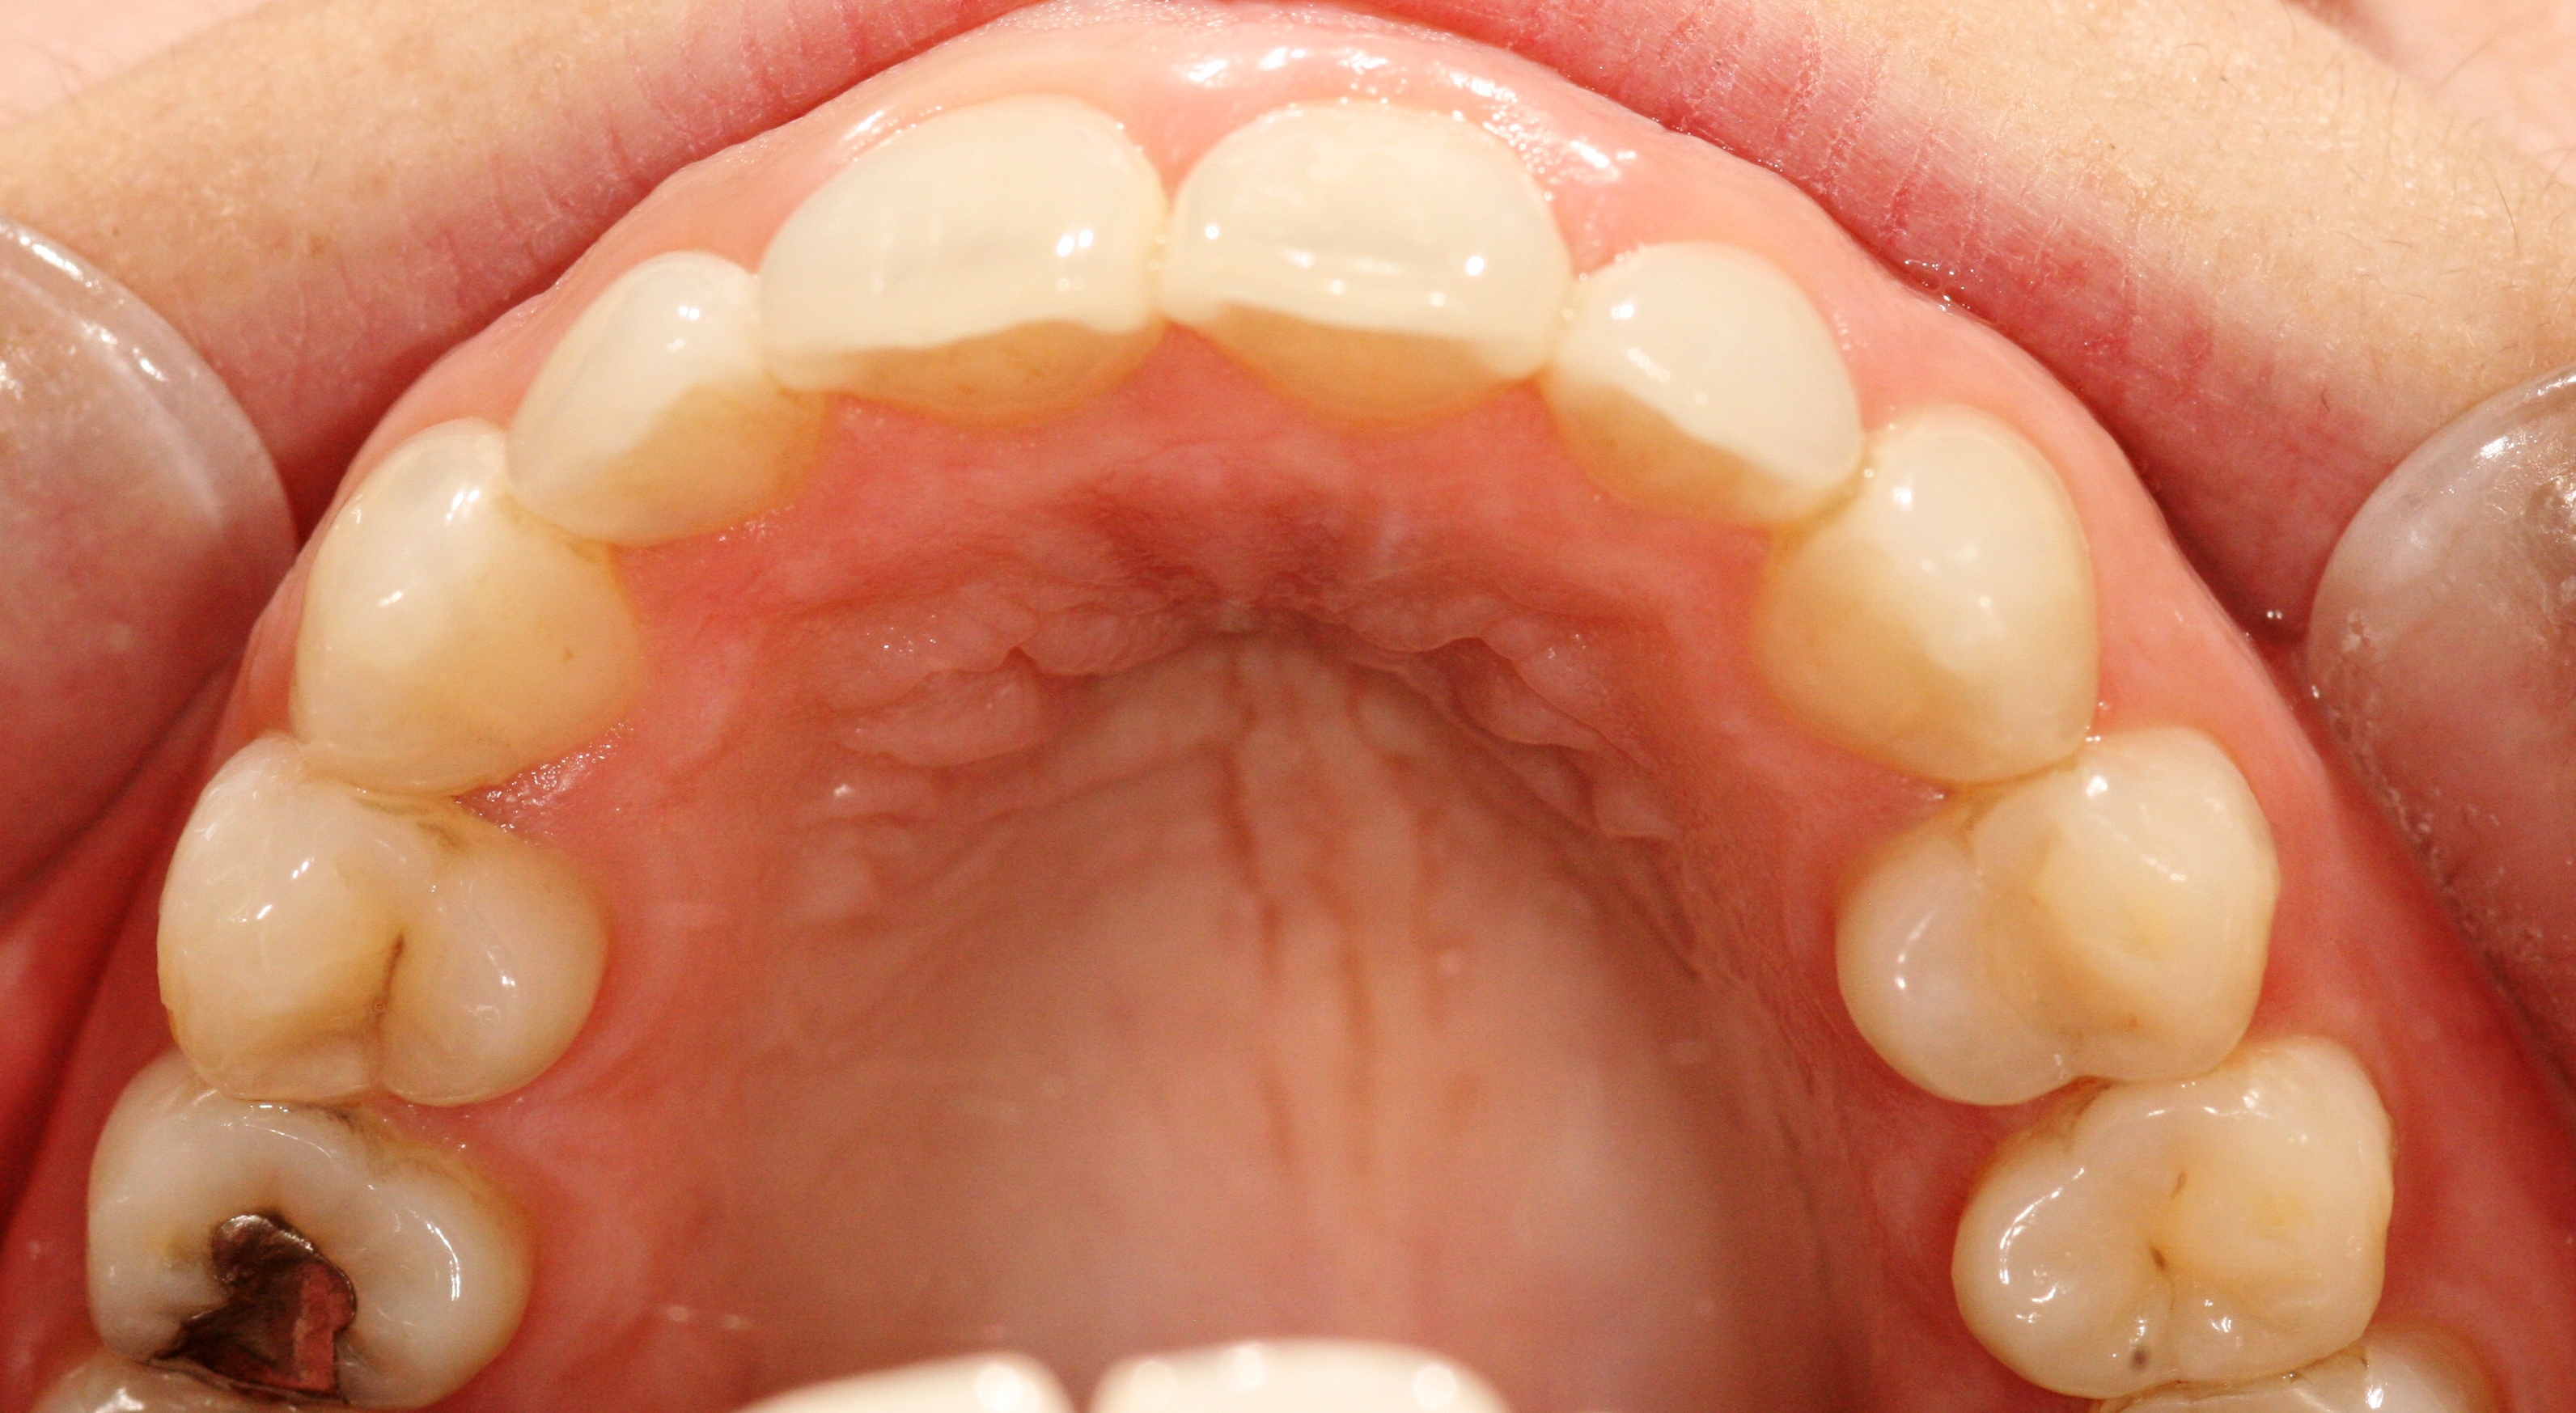

London Dentist Invisalign Braces After

After

Please scroll below for some of our past Invisalign cases: